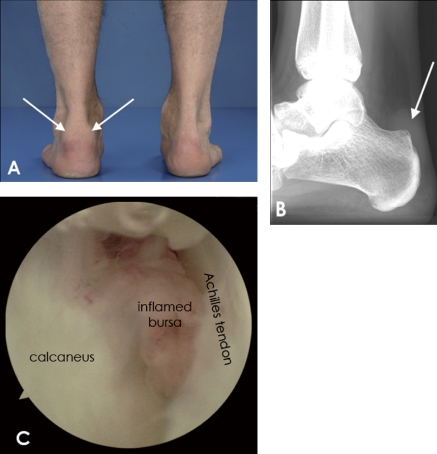

かかとのすぐ上、後ろ側がポコッと腫れて靴に当たると強く痛む場合、滑液包炎の可能性があると言われています。アキレス腱よりも、かかとの骨に近い位置が腫れるのが特徴です。

かかと裏が大きく腫れている場合(滑液包炎)